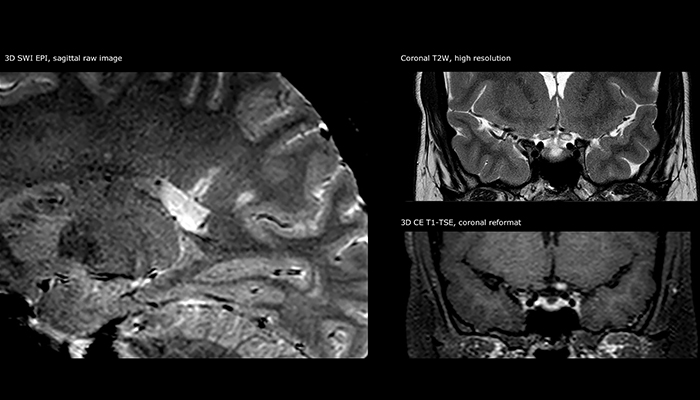

Imaging MS in brain

For MS imaging in the brain, Dr. Savatovsky uses 3D FLAIR as the basic sequence to visualize the lesions and assess the situation and lesion load. “We count the lesions in each location to determine if the criteria of the disease are fulfilled. We use a T2-weighted sequence because our neurologists are used to it. We compare the lesion load on FLAIR with a 3D T1 post-contrast sequence to help us determine whether lesions are old or new. We typically administer the contrast before the patient enters the machine because it shortens the examination time and allows to visualize active lesions that tend to be more visible after several minutes. When a differential diagnosis is difficult, we add sequences such as susceptibility imaging, because some focal MS lesions have a small vein in the center[3].”

“The biggest challenges are properly characterizing the lesion and giving the surgeon all the information needed, such as the location of vessels and functional areas. Sometimes a very comprehensive exam is necessary, such as when a mass has been discovered at another hospital after which the patient is referred to us. We then do both lesion characterization and preoperative imaging in one exam, so both morphologic and functional assessment. For morphologic assessment we will use pre- and post-contrast T1-weighted imaging, FLAIR to assess infiltration, and diffusion. For functional characterization we will perform perfusion, spectroscopy, and susceptibility weighted imaging to look for micro vessels or micro hemorrhage inside the lesion[4]. For preoperative imaging we perform specific morphologic imaging that is compatible with the navigation system; depending on the location of the tumor, we would do fMRI or DTI.”